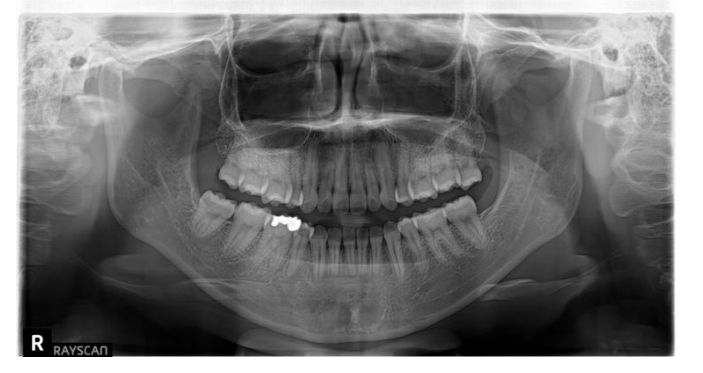

| 設備名 | 役割・特徴 |

| パノラマレントゲン | ・口腔内全体(上下の歯列・顎・顎関節・鼻腔の一部など)を一枚のX線写真に収めることができる |

あらゆる設備をフル活用すれば、以下のように骨格や噛み合わせを立体的に把握できます。その結果、「感覚や経験だけに頼らない、科学的根拠に基づいた矯正」を行うことができるのです。

| 歯列矯正に必要な設備 |

・歯科用CT

・パノラマレントゲン

|

※表内の画像について出典:ミライズ矯正歯科南青山